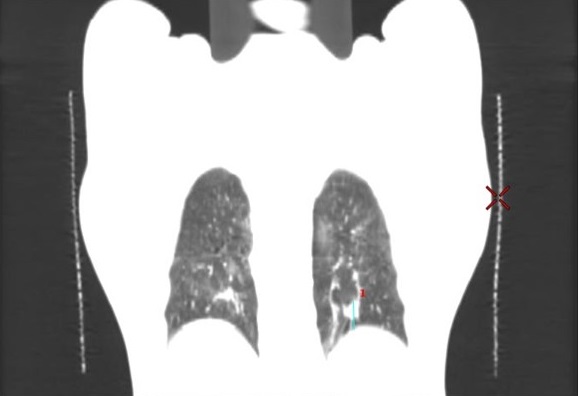

病例资料:男性,62岁,左下肺转移肿瘤。 扫描方法: 常规CT平扫

临床价值:使用4D-CT扫描可以准确评价肿瘤运动范围,确定肿瘤ITV(内靶区)。

在肿瘤最大层面测量,最大径为15.2mm。 4D呼吸门控扫描:

使用D4D呼吸门控扫描,可清楚观察到肿瘤本身随呼吸周期运动的情况。

使用A4D软件测量,肿瘤随呼吸周期的运动幅度近24mm。

扫描结束之后,使用Advantage 4D软件可把图像分成10个呼吸期相,生成MIP图、AveIP图和minIP图。使用Advantage SIM MD软件可以在4D运动的图像上实时勾画和修改靶区,确定肿瘤ITV,比过去凭经验外扩范围的方式,可更精确的确定肿瘤放射治疗的范围。此外,在Advantage SIM MD上勾画的靶区文件为RT DICOM格式,可以发送给TPS(放疗计划系统),TPS不仅可以读取,如有需要还可进行编辑。